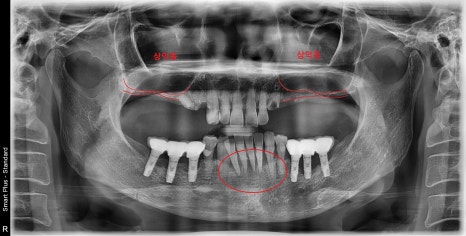

양쪽 어금니가 발치된 지 오래된 상태셨고

위턱뼈의 뼈가 임플란트를 식립하기에는

너무 얇은 상태였습니다.

아래 앞니들은 치주염으로 인한 발치가 필요한 상황이며

위 앞니는 무너진 교합 때문에

앞으로 튀어나고 벌어져 있었습니다.

어금니로의 저작은 불가능하여

제대로 된 식사를 못하시고 계셔서

하루빨리 식사를 하실 수 있게 도와드리고 싶었습니다.